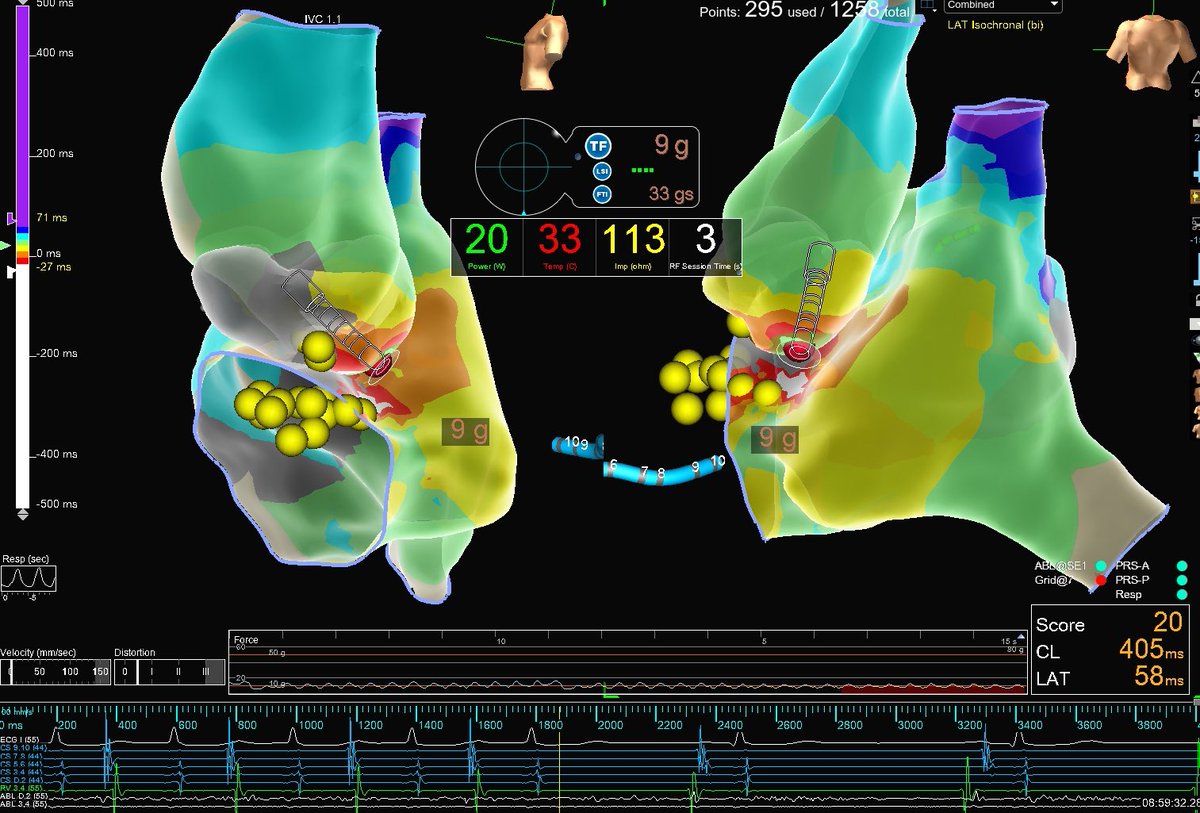

Very cool Atypical AFL. #HDGrid captures entire TCL at area of isochronal crowding. #OT LAT on left vs. bipolar on right 😳. 1 second of RFA terminates & renders SVT non-inducible. Excellent mapping & ablation by Timothy Markman. Map credit: Brian Otto Penn Electrophysiology Fellowship Abbott Cardiovascular

Very cool Atypical AFL. #HDGrid captures entire TCL at area of isochronal crowding. #OT LAT on left vs. bipolar on right 😳. 1 second of RFA terminates &amp; renders SVT non-inducible. Excellent mapping &amp; ablation by <a href="/Dr_Markman/">Timothy Markman</a>. Map credit: <a href="/BrianOttoEP/">Brian Otto</a> <a href="/PennEPFellows/">Penn Electrophysiology Fellowship</a>  <a href="/AbbottCardio/">Abbott Cardiovascular</a>